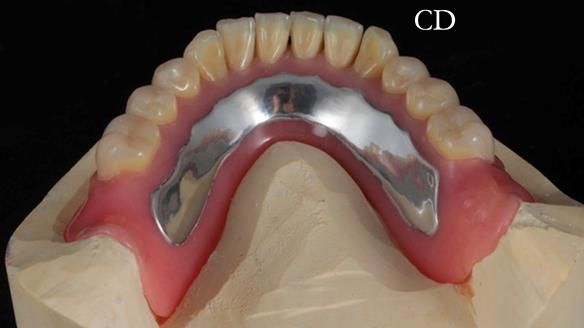

Welcome to Newsletter 62. In this edition, I walk through the process of removing 5 upper anterior teeth, adding to an existing upper RPD, followed by creating and fitting metal based complete dentures for Rafique, a 71 year old man.

The detailed clinical situation and treatment process are outlined below, with clinical work provided by me and technical work by Rowan Garstang. The treatment spanned 12 months, involving removing 5 upper anterior teeth, adding to an existing upper RPD, followed by creating and fitting metal based complete dentures.